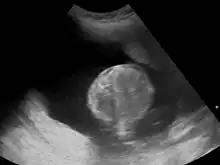

Polyhydramnios is a medical condition describing an excess of amniotic fluid in the amniotic sac. It is seen in about 1% of pregnancies.[1][2][3] It is typically diagnosed when the amniotic fluid index (AFI) is greater than 24 cm.[4][5] There are two clinical varieties of polyhydramnios: chronic polyhydramnios where excess amniotic fluid accumulates gradually, and acute polyhydramnios where excess amniotic fluid collects rapidly.